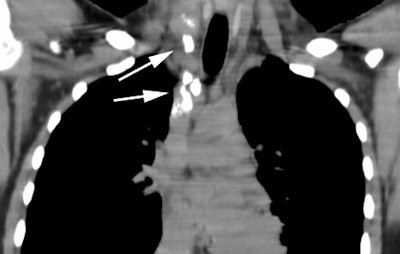

Patients may relapse with pulmonary disease without associated adenopathy. Patients are frequently asymptomatic. In fact, pulmonary involvement will eventually occur in 30-40% of patients with Hodgkins disease. The most common finding is multiple nodules which may contain air-bronchograms. Other findings include lobar or segmental consolidations with air bronchograms that may be indistinguishable from pneumonia (much less common), or a reticular pattern with septal lines due to lymphatic/venous obstruction by bulky adenopathy or from intrinsic tumoral deposits within interstitial lymphatic pathways. Pleural effusions are commonly present.

Computed Tomography: CT can detect intrathoracic sites of disease not detected on CXR in up to 20% of patients. The effect on patient management is quite variable (between 10-60% of patients), and is related to the specific protocol for which the patient is being considered. On CT there is usually an asymmetric, anterior mediastinal soft tissue mass which may invade the chest wall. Bulky mediastinal nodal disease can be associated with interstitial edema due to lymphatic/venous obstruction. Although typically homogeneous, larger masses may contain areas of decreased attenuation representing necrosis or cyst formation. Calcification is RARE prior to therapy. A pleural effusion is seen in up to 30% of cases and is usually felt to be related to lymphatic/venous obstruction from the mediastinal mass [ACR Syllabi #40:p.134 suggests effusions are found in only 2% of cases]. Benign pericardial effusions may also be seen in such patients.